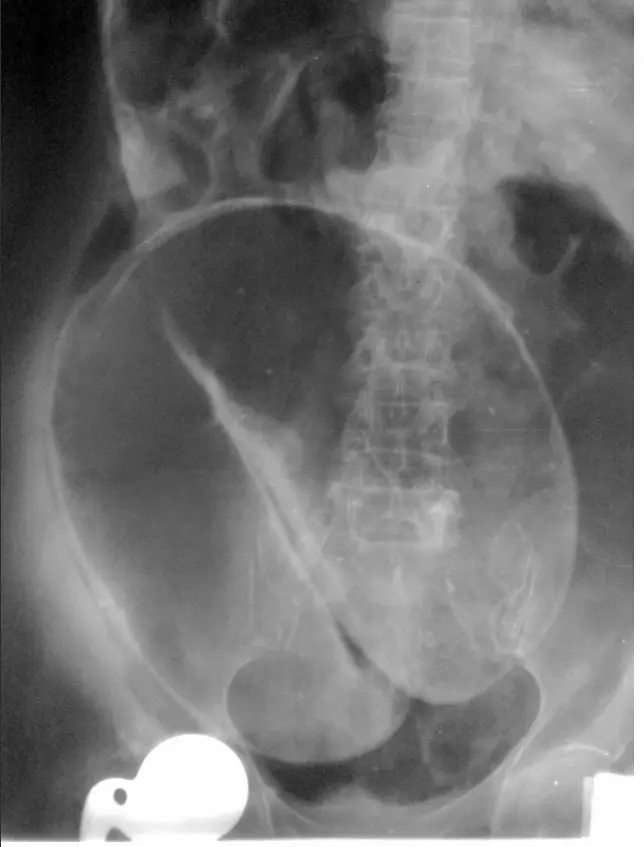

Coffee Bean Sign X-ray: Identifying Sigmoid Volvulus

Sigmoid volvulus is a serious condition causing large bowel obstruction. It occurs when the sigmoid colon twists on its supporting mesentery. A key diagnostic feature seen on X-ray is the ‘coffee bean sign,’ representing the distended, twisted loop of the colo For more cases: visit radiopedia.org